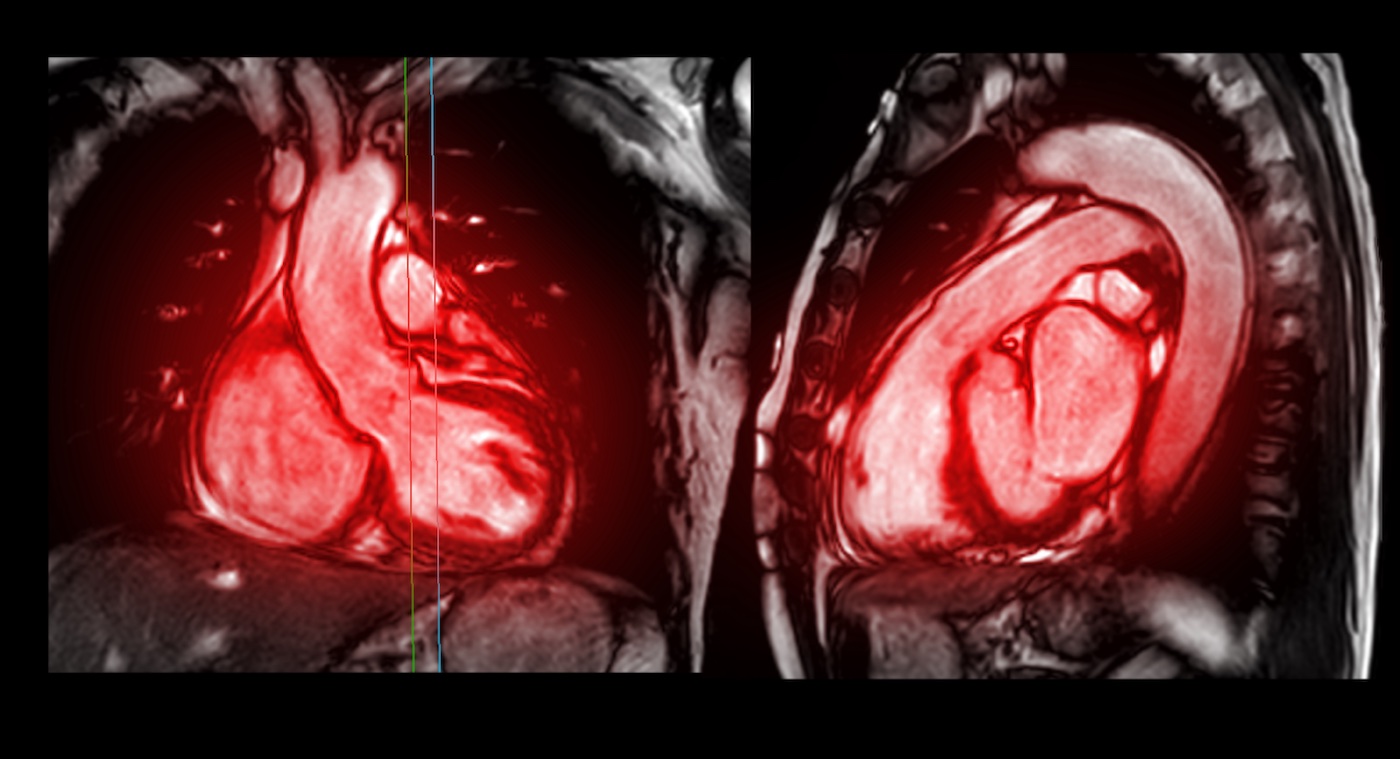

De meest voorkomende tweedimensionale echocardiografische bevindingen waargenomen bij amyloïdose van het hart zijn dilatatie en toegenomen verdikking van de beide atria en van de linker- en rechter ventrikelwand.